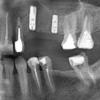

Mila* Опубликовано 15 февраля, 2010 Автор Поделиться Опубликовано 15 февраля, 2010 Нет,это не важно.Можете и двухнедельный(но не тот,фрагмент которого вы показывали)Вот что получилось: моя проблемная зона.Вы были правы, говоря, что боль утихнет.Но хочется, конечно, выяснить ее причину, протезирование отложила. Ссылка на комментарий

annda Опубликовано 15 февраля, 2010 Поделиться Опубликовано 15 февраля, 2010 Вот что получилось: моя проблемная зона.Вы были правы, говоря, что боль утихнет.Но хочется, конечно, выяснить ее причину, протезирование отложила.Имплантики ровненько стоят,их протезируйте,но ведь желательно всё в кучке,верхние и нижний моляры выглядят очень неважно,особенно верхняя 7ка,а что делали с соседним 6м,пломба вроде чуть ли не на устьях стоит,а каналы(аж 4е штуки) не пломбированы ? Ссылка на комментарий

Mila* Опубликовано 16 февраля, 2010 Автор Поделиться Опубликовано 16 февраля, 2010 (изменено) Имплантики ровненько стоят,их протезируйтеannda, это да, но им еще не время.Меня беспокоит 22-й и 4-ка нижняя. Там ничего не видно?особенно верхняя 7ка,а что делали с соседним 6м,пломба вроде чуть ли не на устьях стоит,а каналы(аж 4е штуки) не пломбированы Ну вот их мы уже обсуждали в предыдущей теме про имплантацию, но они пока не беспокоят вообще.а каналы(аж 4е штуки)ого.Вы их видите? Изменено 16 февраля, 2010 пользователем Mila* Ссылка на комментарий

annda Опубликовано 16 февраля, 2010 Поделиться Опубликовано 16 февраля, 2010 Вы их видите?Их там не вижу,их там должно быть...2ка не напрягает,в 4ке возможен дополнительный канал.Но это КТ или серия прицельных снимков с нескольких углов могут точно сказать. Ссылка на комментарий

Снежана Опубликовано 7 марта, 2010 Поделиться Опубликовано 7 марта, 2010 Мила, на представленном вами первом снимке уже есть изменения на корнях, которые говорят о наличии воспаления, размер видимого на снимке очага может отличаться в зависимости от проекции, так что никто вас не обманывает, "киста" действительно уже была.http://s54.radikal.ru/i143/1003/89/870f0a5e2692.gifстрелками я пометила изменения на медиальном корне, но если присмотреться и на дистальном они тоже есть.Комментировать шансы я не буду, слишком от многого это зависит. Ссылка на комментарий

Mila* Опубликовано 7 марта, 2010 Автор Поделиться Опубликовано 7 марта, 2010 стрелками я пометила изменения на медиальном корне, но если присмотреться и на дистальном они тоже есть.Снежана,спасибо.Добавлю, что между депульпированием и этим снимком - прошел один месяц.А на том снимке, который делался в день лечения - никаких затемнений еще нет. Посмотрите, пожалуйста, его. И, естественно, меня никто ни о чем не предупреждал. Комментировать шансы я не буду, слишком от многого это зависит.Хотя бы конспективно, списком.Что видно на втором снимке? Ссылка на комментарий

Снежана Опубликовано 7 марта, 2010 Поделиться Опубликовано 7 марта, 2010 конспективно: от навыков врача, оснащения кабинета, возможностей вашего организма.на этом снимке ничего не видно, но по опыту, такие деструкции как у вас за пару месяцев не образуются, все таки нужен больший срок. Есть немалое количество случаев у разных докторов, когда рентген давал картину мнимого благополучия. Ссылка на комментарий

Mila* Опубликовано 8 марта, 2010 Автор Поделиться Опубликовано 8 марта, 2010 конспективно: от навыков врача, оснащения кабинета, возможностей вашего организма.Снежана, спасибо.такие деструкции как у вас Вот, а какие они, не скажете?Там большой очаг воспаления видно? И у обоих корней? Или не очень? Ссылка на комментарий